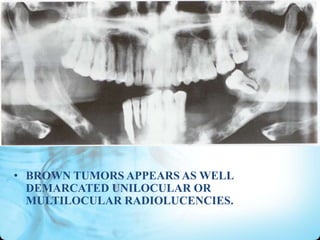

• BROWN TUMORS APPEARS AS WELL

DEMARCATED UNILOCULAR OR

MULTILOCULAR RADIOLUCENCIES.